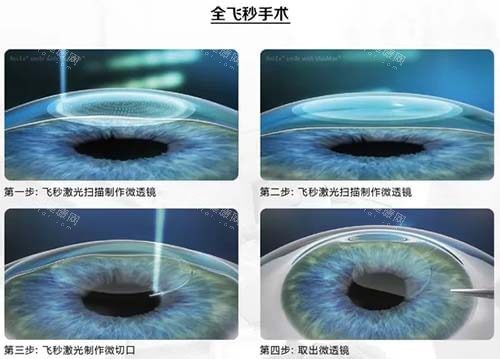

当前主流近视手术分为角膜激光类与眼内晶体植入类,鸡西爱尔眼科医院同步开展全激光(TransPRK)与ICL晶体植入术。两种术式原理差异显著,适应人群各有侧重。

全激光通过准材料激光直接消融角膜上皮与基质层,无需制作角膜瓣,术后生物力学稳定性更优。其核心优势在于:

适应症:适合近视1000度以内、散光600度以内,角膜厚度≥460μm者;

适用人群:军人、运动员等对抗冲击性要求高的人群,或角膜条件不足以支撑半飞秒/全飞秒者;

风险点:术后3-5天疼痛感较明显,需严格遵医嘱用药促进角膜修复。